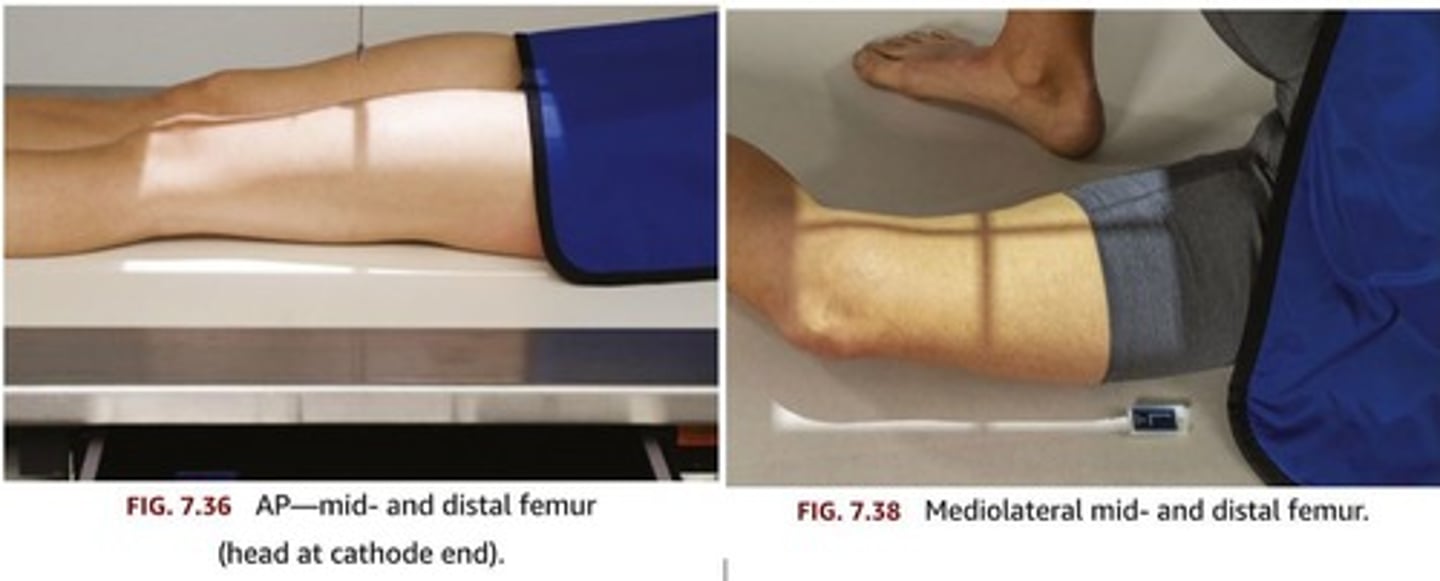

Describe, in detail, how a PATIENT should be positioned for an AP FEMUR projection.

1. Patient lies supine on the x-ray couch and the legs are extended.

2. Posterior aspect of the leg is in contact with the x-ray couch.

3. The IR is placed in the bucky. Make sure that the x-ray tube is locked in with the bucky system.

4. The leg is medially rotated to centralise the patella. The condyles should be equidistant to the IR.

If it is not possible to get both the hip and knee joint on the same IR, then this exposure should be hip down and then a second IR to do an 'out of bucky' knee up exposure.

How should we position the X-RAY TUBE when doing an AP FEMUR projection?

SID

Central ray

Centring point

SID: 100 - 115cm

Central ray: perpendicular to the IR

Centring point: midline of the femur, midway between knee & hip joint.

How should we COLLIMATE when doing an AP FEMUR projection? What structures should be included in the image?

Describe, in detail, how we should position the PATIENT when doing a LATERAL FEMUR projection.

1. Patient is turned onto the affected side, lateral aspect of the leg in contact with the IR.

2. Femur oriented diagonally across an IR if 'out of bucky'.

3. Knee joint flexed and condyles should be superimposed.

4. Pelvis rotated backwards to separate the thighs.

5. Hip down image on second IR in bucky (if not possible to get both joints on one IR)